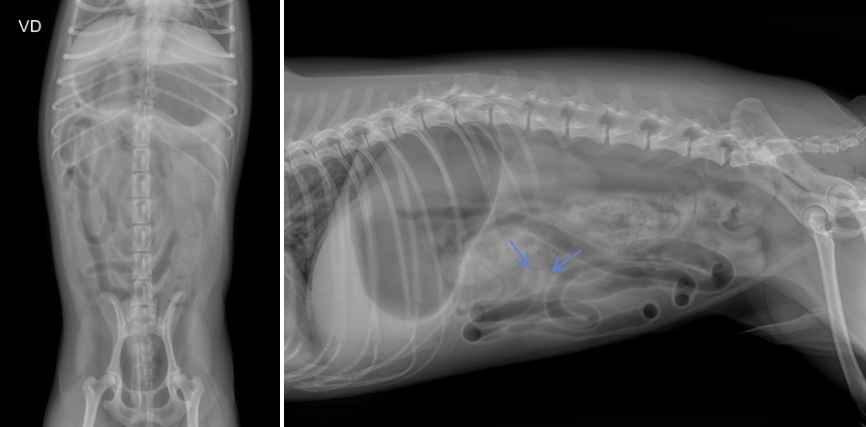

하지만 방사선 검사는 이물 진단의 민감도와 특이도가 약 66% 수준으로 단독으로는 정확도가 높지 않습니다.

실제로 이 환자의 경우, 방사선상 씨앗 형태의 이물로 의심되는 희미한 음영이 관찰되었으나 음영이 뚜렷하지 않았고 소장의 명확한 확장 소견도 확인되지 않아 단순 방사선만으로는 이물에 의한 폐색을 확정하기 어려운 상황이었습니다.

따라서 이런 경우에는 복부 초음파 검사를 추가로 시행하여 이물 자체의 위치와 형태, 장벽의 두께 변화, 장 운동성, 폐색 부위 전후의 확장 정도 등을 평가함으로써 진단의 정확도를 높이는 것이 필요했습니다.